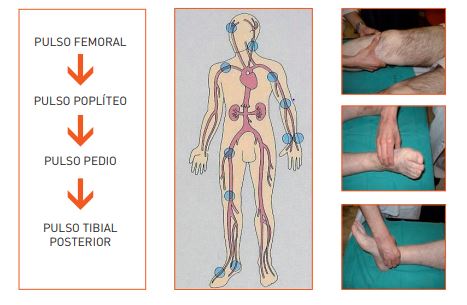

Palpamos cuidadosamente los pulsos en la arteria femoral (por debajo del pliegue inguinal), en la arteria poplíteo (se encuentra en el hueco poplíteo, con la rodilla flexionada a 300), en la arteria tibial posterior (detrás del maléolo interno) y en la arteria pedia (en el dorso del pie, entre el primero y el segundo metatarsianos). Realizamos la palpación de los pulsos con los dedos y con la ayuda de un Doppler. Evaluamos los pulsos por su frecuencia, su ritmo, amplitud y comparando entre el izquierdo/derecho. Se pueden clasificar como ausentes, disminuidos o presentes.

La ausencia de pulso tibial posterior es el mejor discriminador aislado de la isquemia crónica (dado que falta raramente en personas sin daño).2

Imagen 3